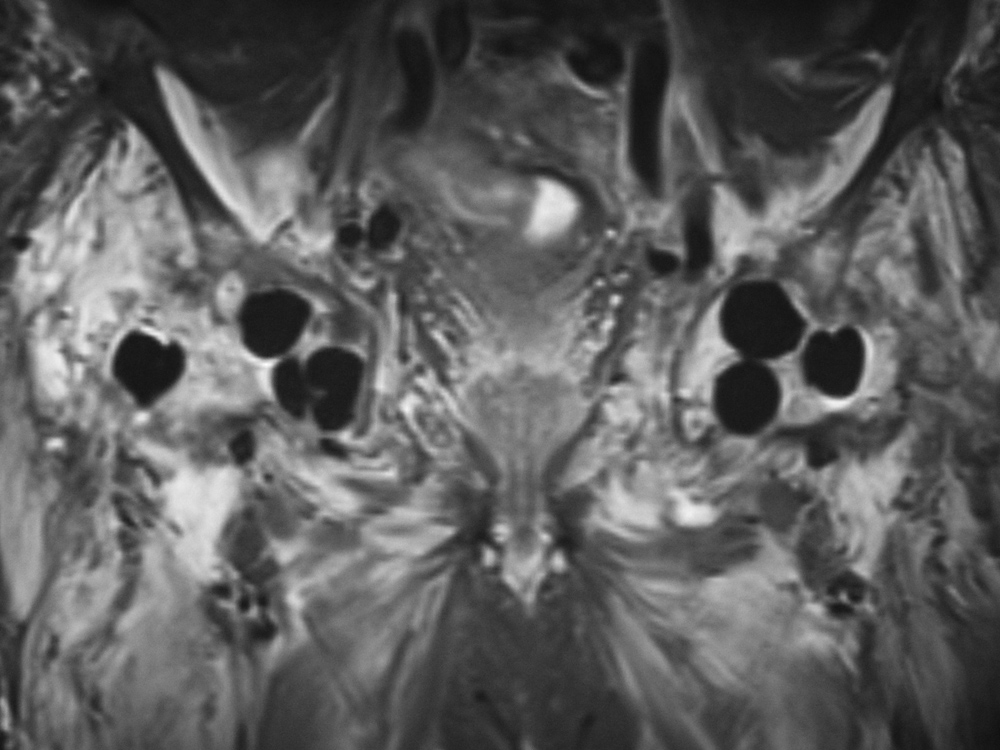

Bilateral hip antibiotic beads in a patient with infected hips after girdlestone procedures

Later coronal STIR MRI image. The beads have low signal and would not be recognizable without radiographic correlation.